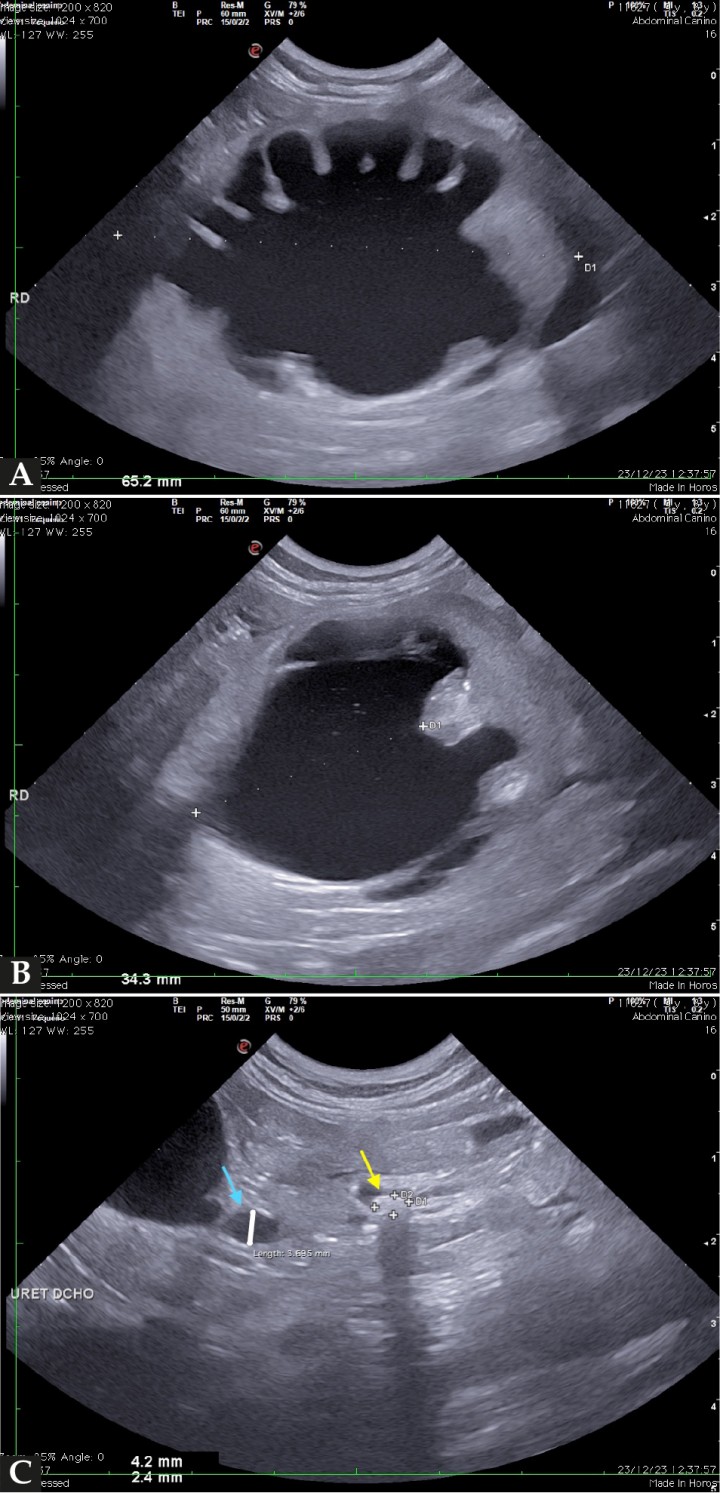

Con respecto al riñón izquierdo, el parénquima renal se observaba hiperecoico, con pérdida marcada de diferenciación corticomedular y un tamaño renal normal (3,7 cm); la pelvis renal se observó dilatada (0,85 cm) y en su interior se identificó una estructura hiperecoica, alargada, de 0,75 cm de longitud y bordes mal definidos que generaba una fuerte sombra acústica distal (Fig. 4A). El uréter izquierdo estaba ligeramente distendido (0,15 cm), con presencia de material ecogénico de pequeño tamaño en su interior, aparentemente no obstructivo, que no generaba sombra acústica distal.

(A) Imagen ecográfica del riñón izquierdo en corte transversal en la que se observa un aumento marcado de la ecogenicidad del parénquima renal, con pérdida de diferenciación corticomedular y la presencia de un renolito de 7,5 mm (entre cursores), que genera sombra acústica distal. (B) Imagen ecográfica de la vejiga de la orina severamente distendida con material ecogénico de pequeño tamaño en suspensión. (C) Imagen ecográfica de la uretra proximal en corte longitudinal con una dilatación de casi 2 mm.

La vejiga de la orina se observó marcadamente distendida, con presencia de ligera cantidad de contenido ecogénico en suspensión, sin identificar estructuras ecogénicas de mayor tamaño que generasen sombra acústica distal (Fig. 4B). La uretra valorable ecográficamente se observó dilatada (3 mm), sin evidenciar material ecogénico en dicho tramo y no pudiendo descartarlo en la porción distal no valorable (Fig. 4C). El peritoneo adyacente se encontraba hiperecoico, engrosado y con una leve cantidad de líquido libre tanto perivesical como retroperitoneal.

El diagnóstico presuntivo fue compatible con obstrucción ureteral derecha por ureterolitos con hidronefrosis secundaria, así como obstrucción uretral concomitante por abundante material mineral en uretra distal (identificado radiológicamente). El renolito del riñón izquierdo no parecía obstructivo en el momento del estudio, aunque no se podía descartar completamente. Los cambios degenerativos identificados en el riñón izquierdo fueron compatibles con nefritis intersticial crónica como diagnóstico más probable.